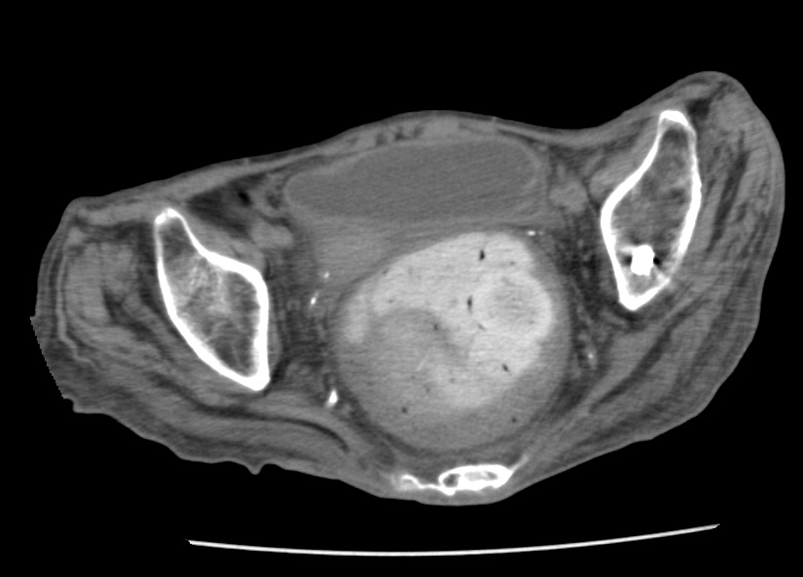

腹部単純CT:

腹部エコー:膀胱内に尿貯留著明

→初療医により導尿施行され多量の尿回収あり、その後下腹部痛は改善した